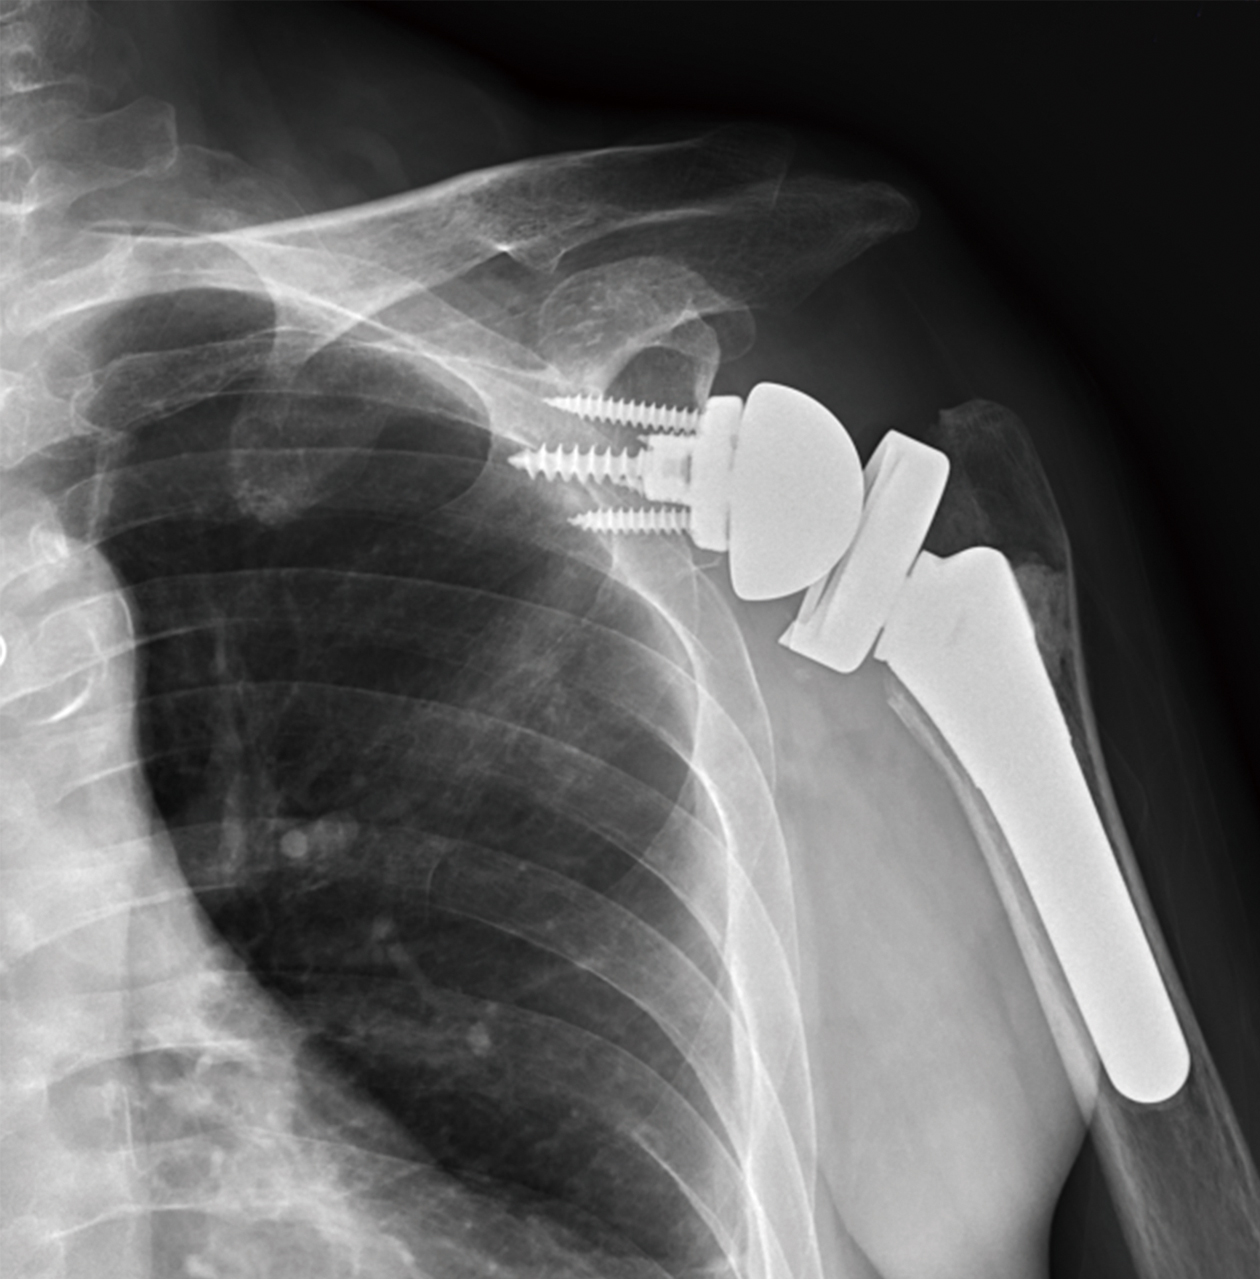

謝陳女士74歲,右肩關節疼痛一年以上,活動受限,手臂無力上舉,經檢查發現右肩關節炎,旋轉肌腱大片全層破裂內縮,接受反置式人工全肩關節置換術,術後疼痛緩解,活動角度可達140度以上。

右肩關節炎合併旋轉肌腱斷裂,經反置式人工全肩關節置換手術治療。